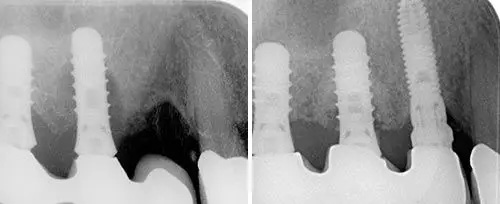

Periodontics